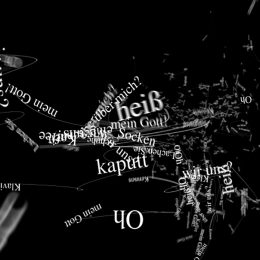

Bist du meine Frau?

In Zusammenarbeit mit der Hamburger Agentur Jung von Matt hat gate.11 einen Kinospot für die Alzheimer Forschung Initiative e.V. entwickelt. Er nimmt den Betrachter mit durch Fragmente und Gedankenwelten eines Alzheimer-Patienten. Ein virtueller Einblick, der die Dramatik dieser Krankheit einfühlvoll vermittelt.